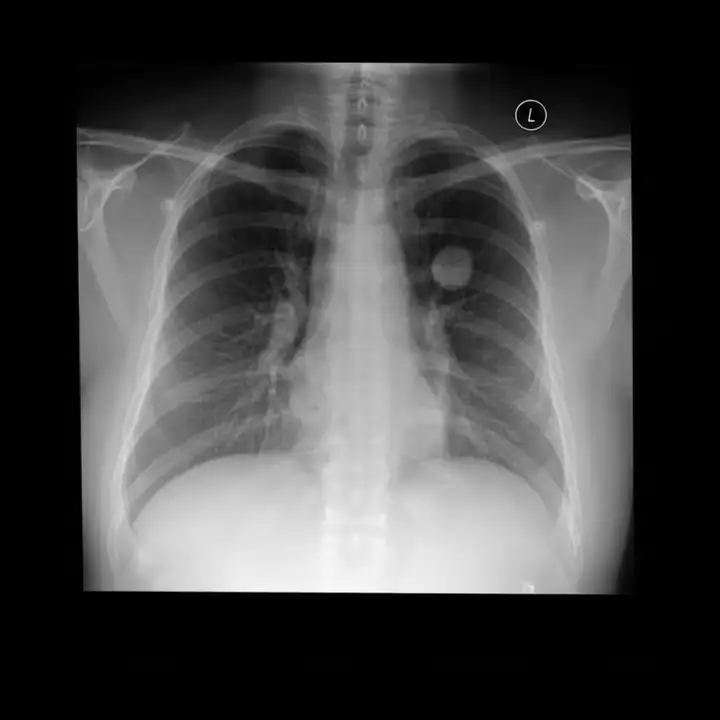

Med-Banana-50K 是一个面向文本引导医学影像编辑任务的大规模数据集,旨在支持多模态模型在不同医学影像模态与疾病条件下的病灶编辑能力研究。数据集包含超过 50,000 条医学影像编辑样本,并额外提供约 37,000 条失败编辑尝试及其完整评估日志,覆盖胸部 X 光、脑部 MRI 与眼底影像三种模态以及 23 种疾病类型。所有样本均支持病灶添加与去除两种编辑方向,并附带基于自动评估流程生成的多维质量判定结果,适合用于医学图像编辑、模型评测与误差分析研究。

数据集示例